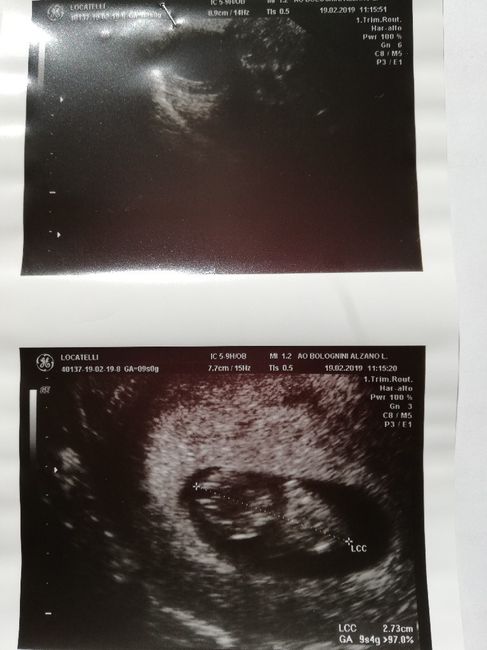

Ciao a tutte mamme e future mamme! Qualcuna conosce il metodo Ramzi? Ho fatto eco interna ieri a 7+3, procede tutto bene e ora sono curiosa di sapere cosa potrebbe essere il mio fagiolino! ❤ grazie a chi mi risponderà

Ciao a tutte...prima eco interna fatta a 7+2...voi che dite....potrebbe essere maschio o femmina?

Se ho capito bene il metodo e se quella parte più chiara a sinistra è la placenta, dovrebbe essere femmina🙂

Questa è la mia a9settimane... Io non capisco.. Qualcuno sa dirmi?

In base alla posizione della placenta, credo, si può predire il sesso del bimbo.... ho trovato questa immagine che spiega il metodo in base ad una ecografia interna!

É messa male la eco..? Mi sembra sia capovolta...? Cmq se fosse capovolta sarebbe una femmina... Se invece è giusta cosi direi maschio...